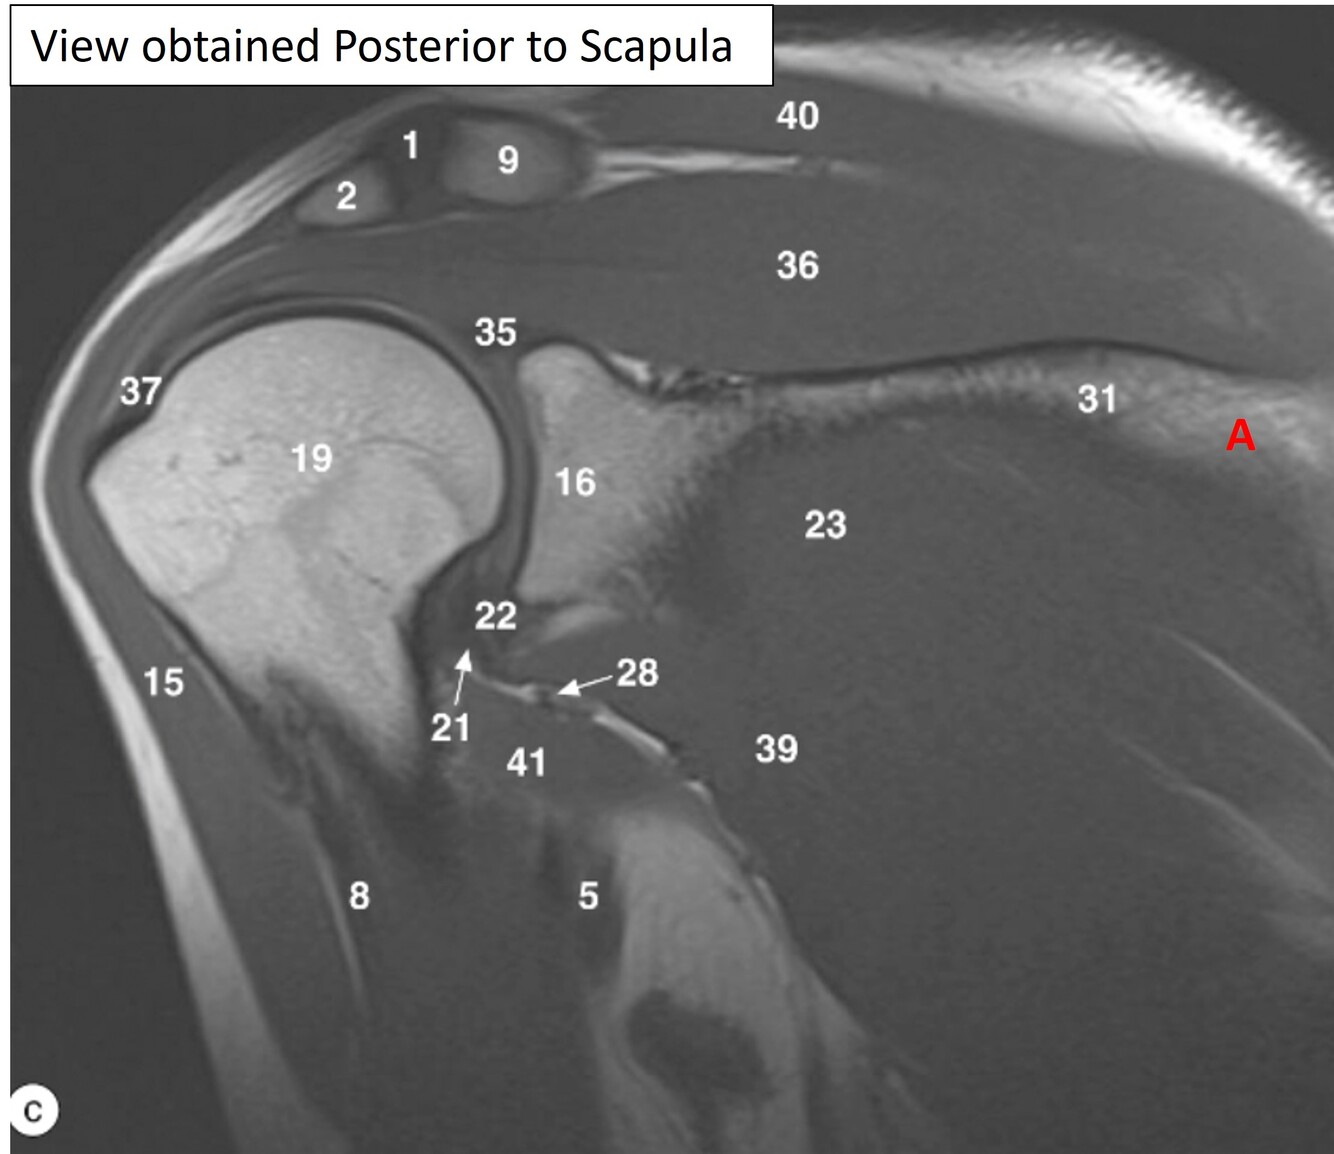

Label 1,2,9,15,36,40

Label 16,18,19,23

A

16=Glenoid process of Rt. scapula

18=Greater tubercle of Rt. humerus

19=Head of rt. humerus

23=Rt. infraspinatus muscle

Q

Label 13,15,16,18,19,23,32

13=Rt. coracoid process

15=Rt. deltoid muscle

23= Rt. infraspinatus muscle

32=Rt. subscapularis muscle

Label 1,2,9,15,16,19

1=Rt. AC joint

2=Acromion of rt. scapula

9=Rt. clavicle (acromial end)

Label 23, 31,36,39,40

31=Spine of rt. scapula

36-Rt. supraspinatus muscle

39=Rt. teres minor

40=Rt. trapezius muscle

Label a

Supraspinous fossa